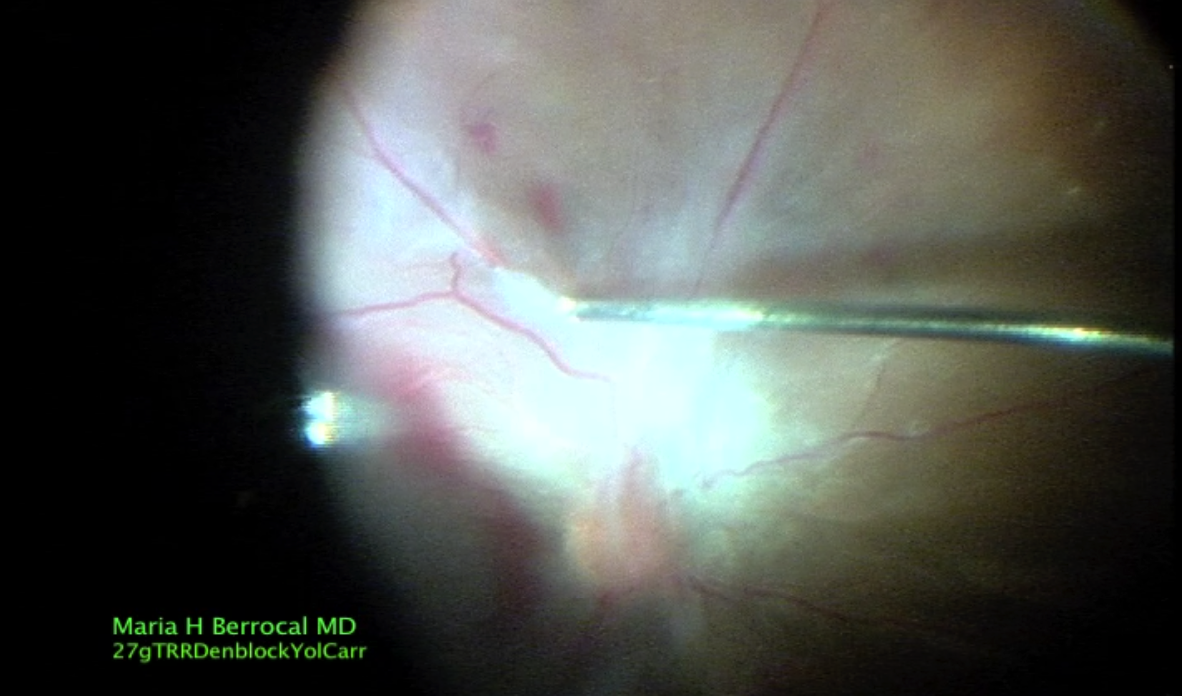

Dr. Berrocal 27G HyperVit TRD VH w/ DATAFUSION

Maria Berrocal, MD